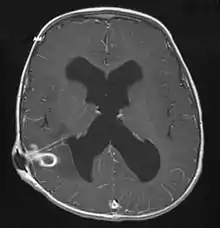

Brain abscess in a person with a CSF shunt. The abscess is the darker gray region in the lower left of the image (corresponding to the right parietal lobe). The lateral ventricles are visible in black in the center of the brain, adjacent to the abscess.[1]

MRI (T1 with contrast) showing the ring-enhancing lesion. From a rare case report of an abscess formed as a complication of the CSF shunt. Jamjoom et al., 2009.[1]